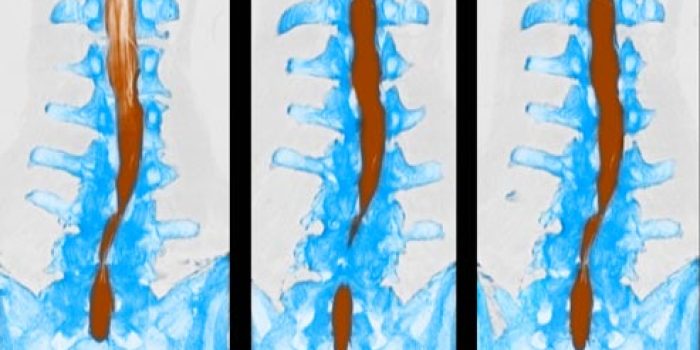

تشخیص دیسک کم با اسکن MRI

در این روش از میدان مغناطیسی برای گرفتن عکس از بدن استفاده می شود. با کمک این تست می توان به طور قطعی محل فتق دیسک کمر را شناسایی کرد و عصب تحت فشار را یافت.

تشخیص دیسک کمر با سی تی اسکن

بوسیله اشعه ایکس ، عکسی از مقطع ستون فقرات و اجزای اطراف آن برای تشخیص دیسک کمرتهیه می شود.

تشخیص دیسک کمر با میلوگرام

رنگی درون مایع نخاعی تزریق شده و سپس اشعه ایکس به آن تابانده می شود. این آزمایش می تواند نشان دهنده فشار بر روی نخاع یا عصب بر اثر فتق دیسک کمر یا دلایل دیگر باشد.